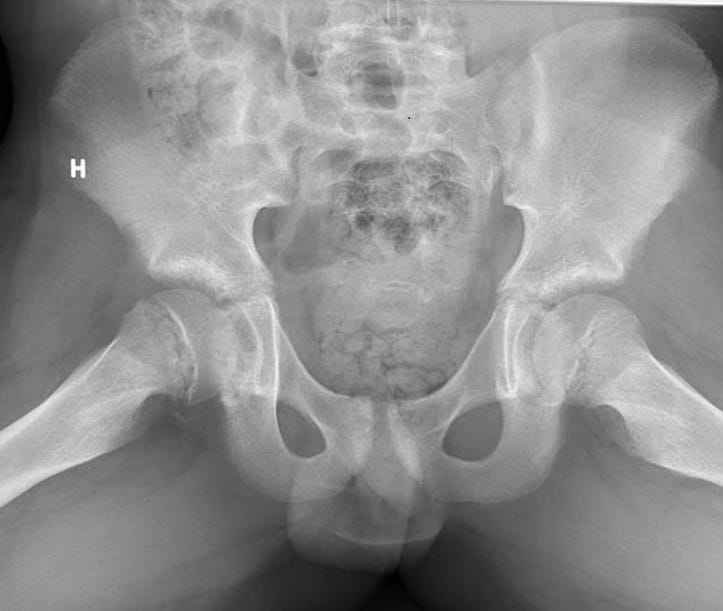

Avulsion injuries of the pelvis are a frequent cause of hip pain in adolescents involved in sports. Because at this age the tendons are generally stronger than the apophyses, strong muscle contraction can result in apophyseal avulsion fractures (Fig.6). Avulsion injuries can be acute or chronic.

Figure 6. Sites of common avulsion injuries and muscle attachments.